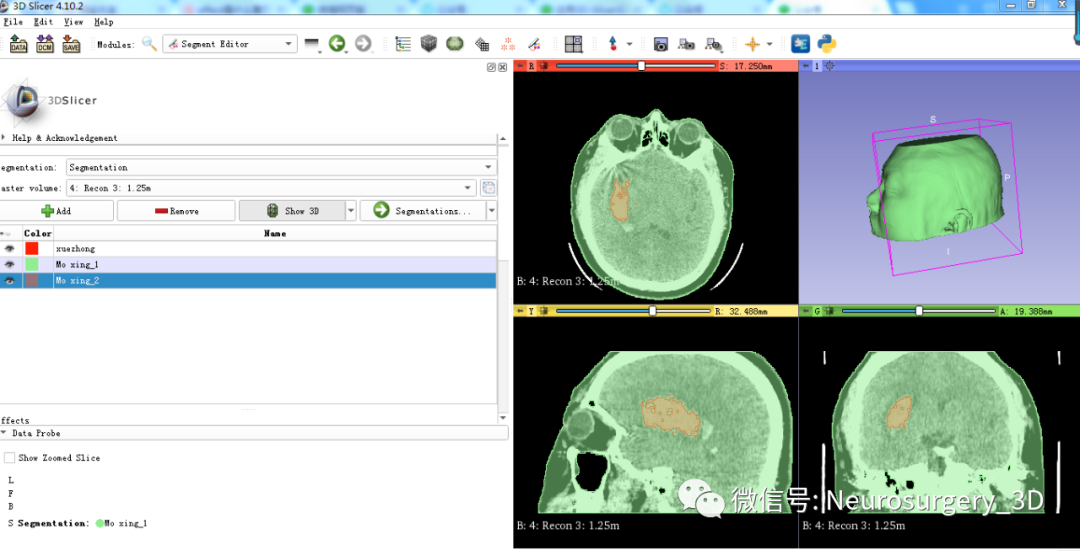

1、在同等阈值-200至3071状态下增加设置segment_1、segment_2并重新命名为Mo xing_1、Mo xing_2。

2、利用Margin![]() 中的Grow膨胀Mo xing_2,可见图中红褐色大于绿色模型。

中的Grow膨胀Mo xing_2,可见图中红褐色大于绿色模型。